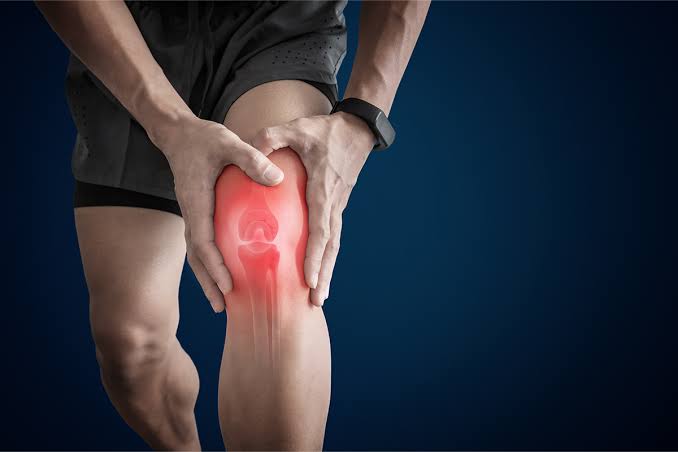

Knee Osteoarthritis

Total Knee Replacement

Chondromalacia Patella

Knee Bursitis

Anterior Cruciate Ligament Tear